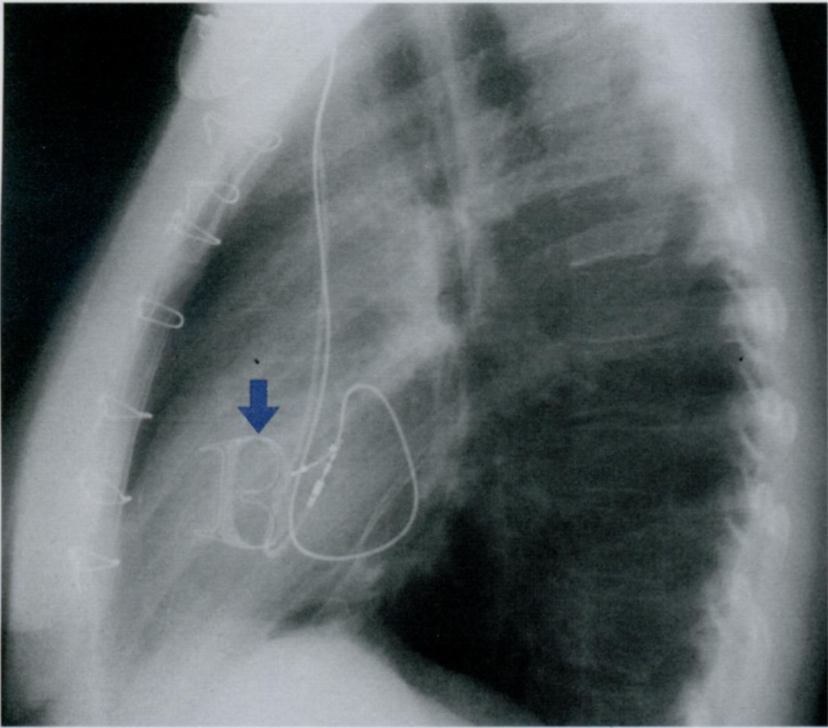

Оцените Rx снимок. Предположите, какую структуру мы видим?

Первичное поражение трехстворчатого клапана, ранее очень редкое, в последние годы участилось в связи с ростом наркомании.

Инфекционное поражение клапана часто развивается после внутривенных инъекций с нестирильными иглами. На Rx показан пример трикуспидальной недостаточности, сопровождающейся стойкой брадиаритмией у женщины-наркоманки.

В данном случае проведено протезирование клапана (стрелка смотрит вниз) и имплантация искусственного вводителя ритма.